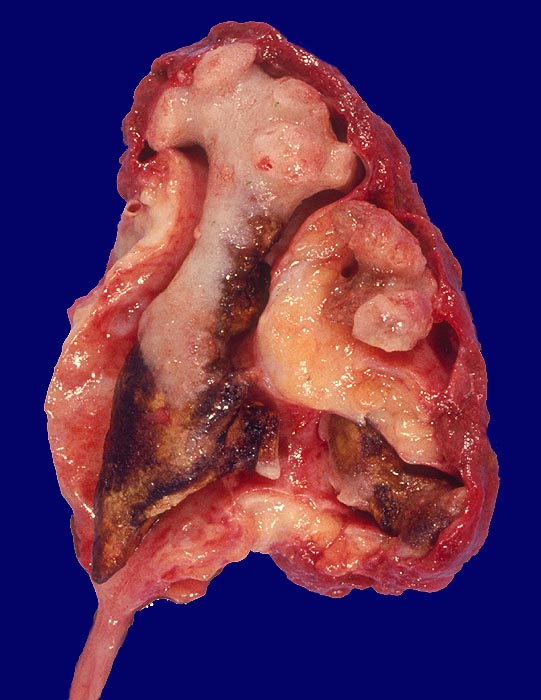

PathoPic – image database / PathoPic ID 1687 - Nierenbeckenausgussstein. Chronische Pyelonephritis.

Nierenbeckenausgussstein. Chronische Pyelonephritis.

Hirschgeweihartiger Nierenbeckenausgussstein. Hochgradige Ausweitung des Nierenbeckens und Schrumpfung des Nierenparenchyms. Die Nierenoberfläche grob gebuckelt infolge rezidivierter Pyelonephritis. Nierenbeckenschleimhaut gerötet.